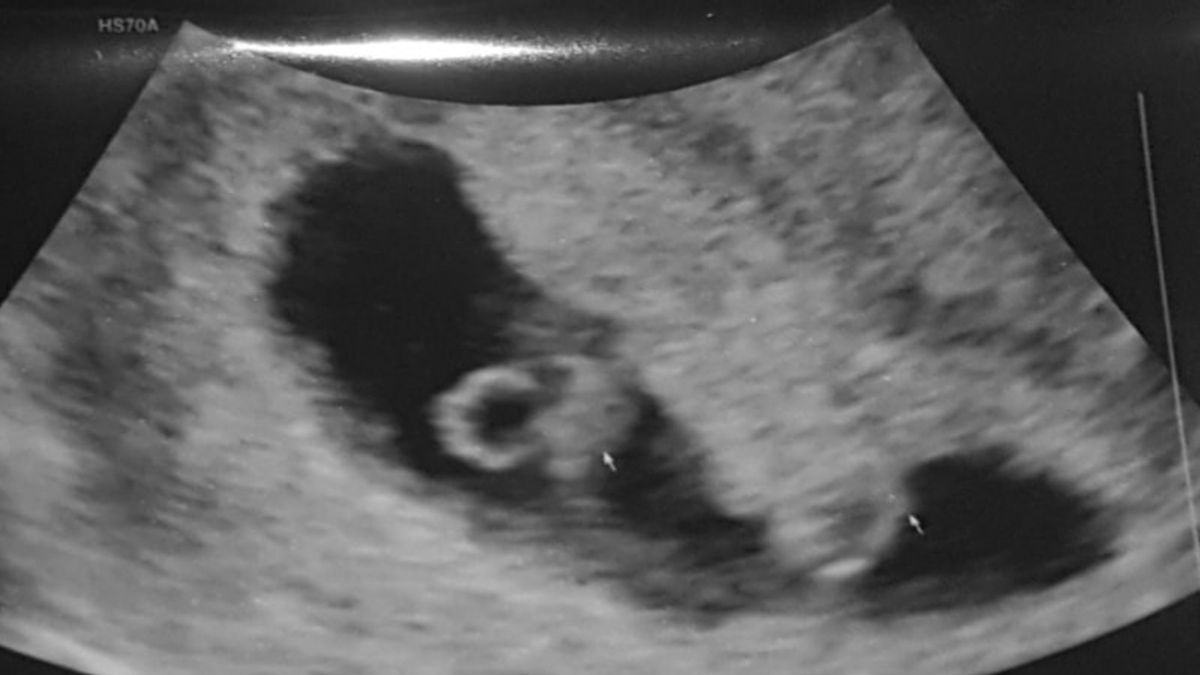

Na acht maanden hadden we een positieve zwangerschapstest, dolgelukkig, het is gelukt, wij worden papa en mama! Al snel daarna mochten we langs komen voor onze eerste echo. Super spannend. Na een gesprek met onze verloskundige werd de echo gemaakt. Ze zag een mooi hartje kloppen er viel een stilte … Ze bewoog een tijdje met haar echo-apparaat… “Ik moet jullie iets vertellen”, zei ze, “ik zie nog een hartje!”. Vol schrik keken mijn vriend en ik elkaar aan. Wtf! Een tweeling?! Onze verloskundige zei: “Gefeliciteerd!”. Met grote ogen keken we haar aan. Het had 24 uur nodig om dit nieuws te laten bezinken. We waren dolblij. Wij kunnen dit! Wat een geluk, we krijgen twee wondertjes! Al snel kwamen alle zwangerschapskwaaltjes opzetten.

Er stond een mooie vakantie in de planning naar Curaçao. Voordat we daar heen gingen, kregen we met 13 weken ons volgende termijnecho. Ik voelde me goed. Zoals het hoort: zwanger, erg moe en misselijk. Maar helaas had de verloskundige slecht nieuws. Alle twee de hartjes waren gestopt. Ik vond het vreemd, want ik had helemaal geen bloedverlies gehad. Toch legde ik me erbij neer.